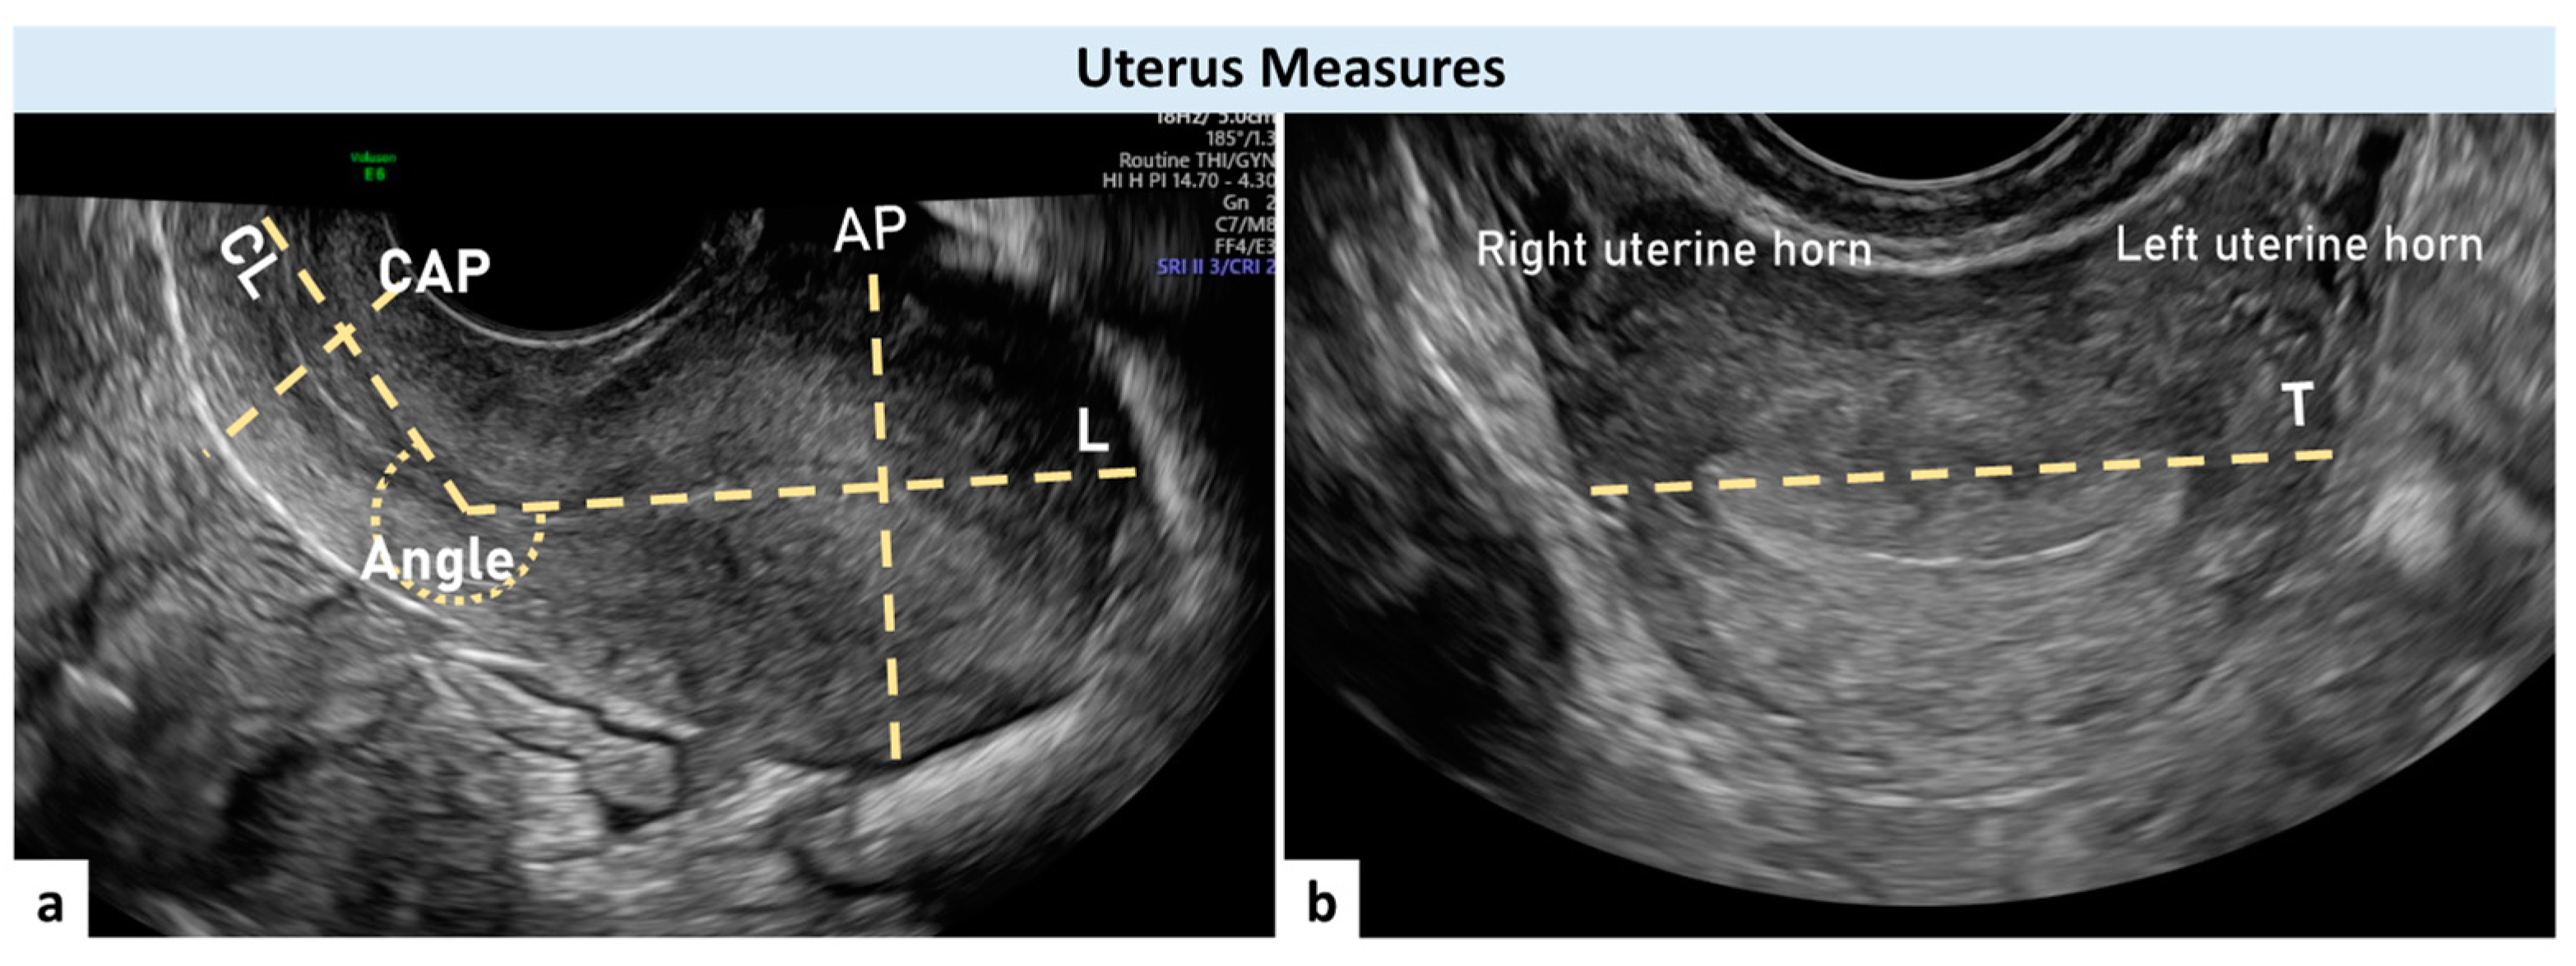

| Uterus L (mm) | 59.5 ± 13.6 |

| Uterus AP (mm) | 39.0 ± 10.4 |

| Uterus T (mm) | 50.9 ± 10.5 |